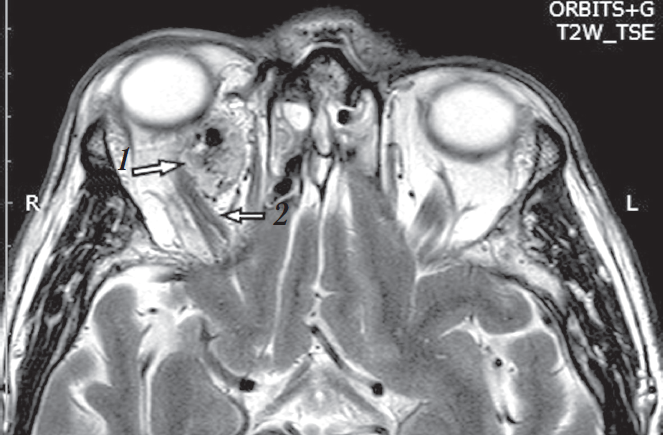

На догоспитальном этапе выполнены МРТ обеих глазниц с реконструкцией в трёх стандартных проекциях. Заключение: «Опухолевый процесс медиальной половины ретробульбарного пространства правой глазницы с признаками экзофтальма» (рис. 9).

Рис. 9. Магнитно-резонансная томограмма Т2 ВИ, аксиальная (a) и сагиттальная (b) проекции. Новообразование правой глазницы (указано стрелкой)

Fig. 9. Magnetic resonance imaging T2 WI, axial (a) and sagittal (b) projections. Neoplasm of the right orbit (arrow)

По данным МРТ с введением контрастного вещества в верхнемедиальном отделе правой глазницы определяется участок структурных изменений с патологически расширенными и извитыми сосудами и эффектом «пустоты потока», характеризующийся неоднородным преимущественно изогиперинтенсивным МР-сигналом на Т2 и Т1 ВИ размером 20 × 17 × 19 мм. Зона патологических изменений интимно прилежит к верхней прямой, верхней косой и медиальной прямой глазным мышцам, оттесняя их. Сверху прилежит к глазному нерву, несколько оттесняя его книзу. Признаки инвазии этих структур отсутствуют. Правая верхняя глазная вена расширена до 5 мм, МР-сигнал от неё повышен на Т2 ВИ, наиболее вероятно, за счёт тромбоза. После внутривенного введения парамагнитного контрастного вещества отмечается его неоднородное, умеренно интенсивное накопление вышеописанной зоной структурных изменений. Задний край правого глазного яблока расположен на уровне межскуловой линии, левого — кзади от межскуловой линии до 7,5 мм (рис. 11).

Рис. 11. Магнитно-резонансная томограмма Т2 ВИ, аксиальная проекция. Образование в правой глазнице (1), расширенная верхняя глазная вена (2)

Fig. 11. Magnetic resonance imaging T2 WI, axial projection. Tumor in the right orbit (1), dilated upper ophthalmic vein (2)